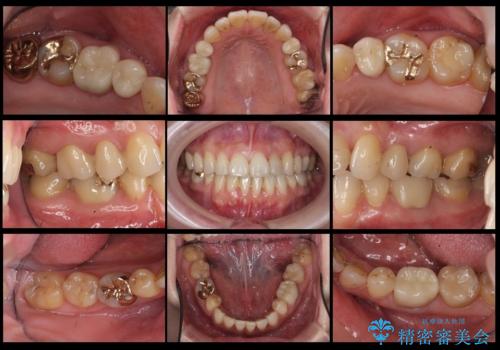

右上7・左上6:PGAインレー

右上8:PGAクラウン

左上4・左下6・右上56:ジルコニアクラウン

左上7・左下7:emaxインレー

での治療を行っています。

根管治療はDr.大元が行っています。